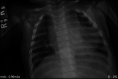

Reports thus far suggest a mild course for acute COVID-19 infection in children; however, its effects in vulnerable paediatric populations, including children with haemodynamically significant congenital heart disease, have rarely been reported. We therefore report on a 4-month-old Hispanic male with a moderate sized conoventricular ventricular septal defect and pulmonary overcirculation who presented with COVID-19-associated pneumonia.